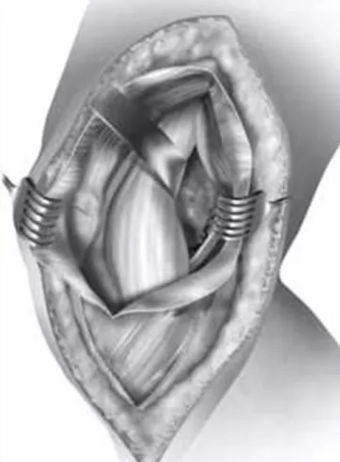

骨与软组织并重:Hoffa骨折往往也伴有肌腱、韧带附着点的损伤,故对这些组织结构的解剖复位对恢复膝关节的稳定性和功能也至关重要。

(Hoffa合并PCL损伤一期修复)